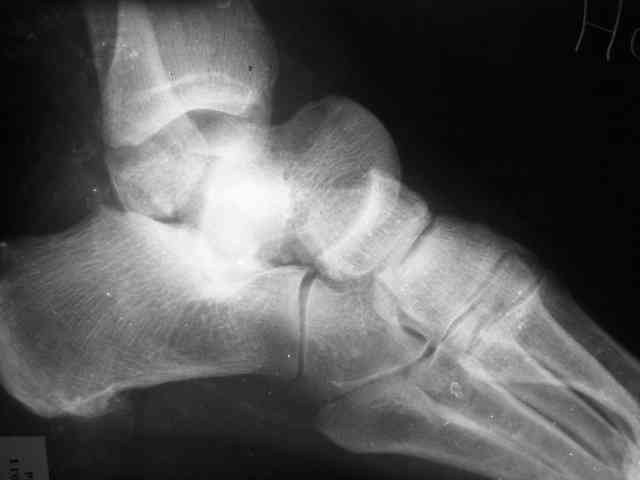

Уважаемый Александр! Как обещал представляю Р-граммы и операционные фото.

Последний снимок

Мнение по поводу тарана? АН есть?

Типичная картина некроза.